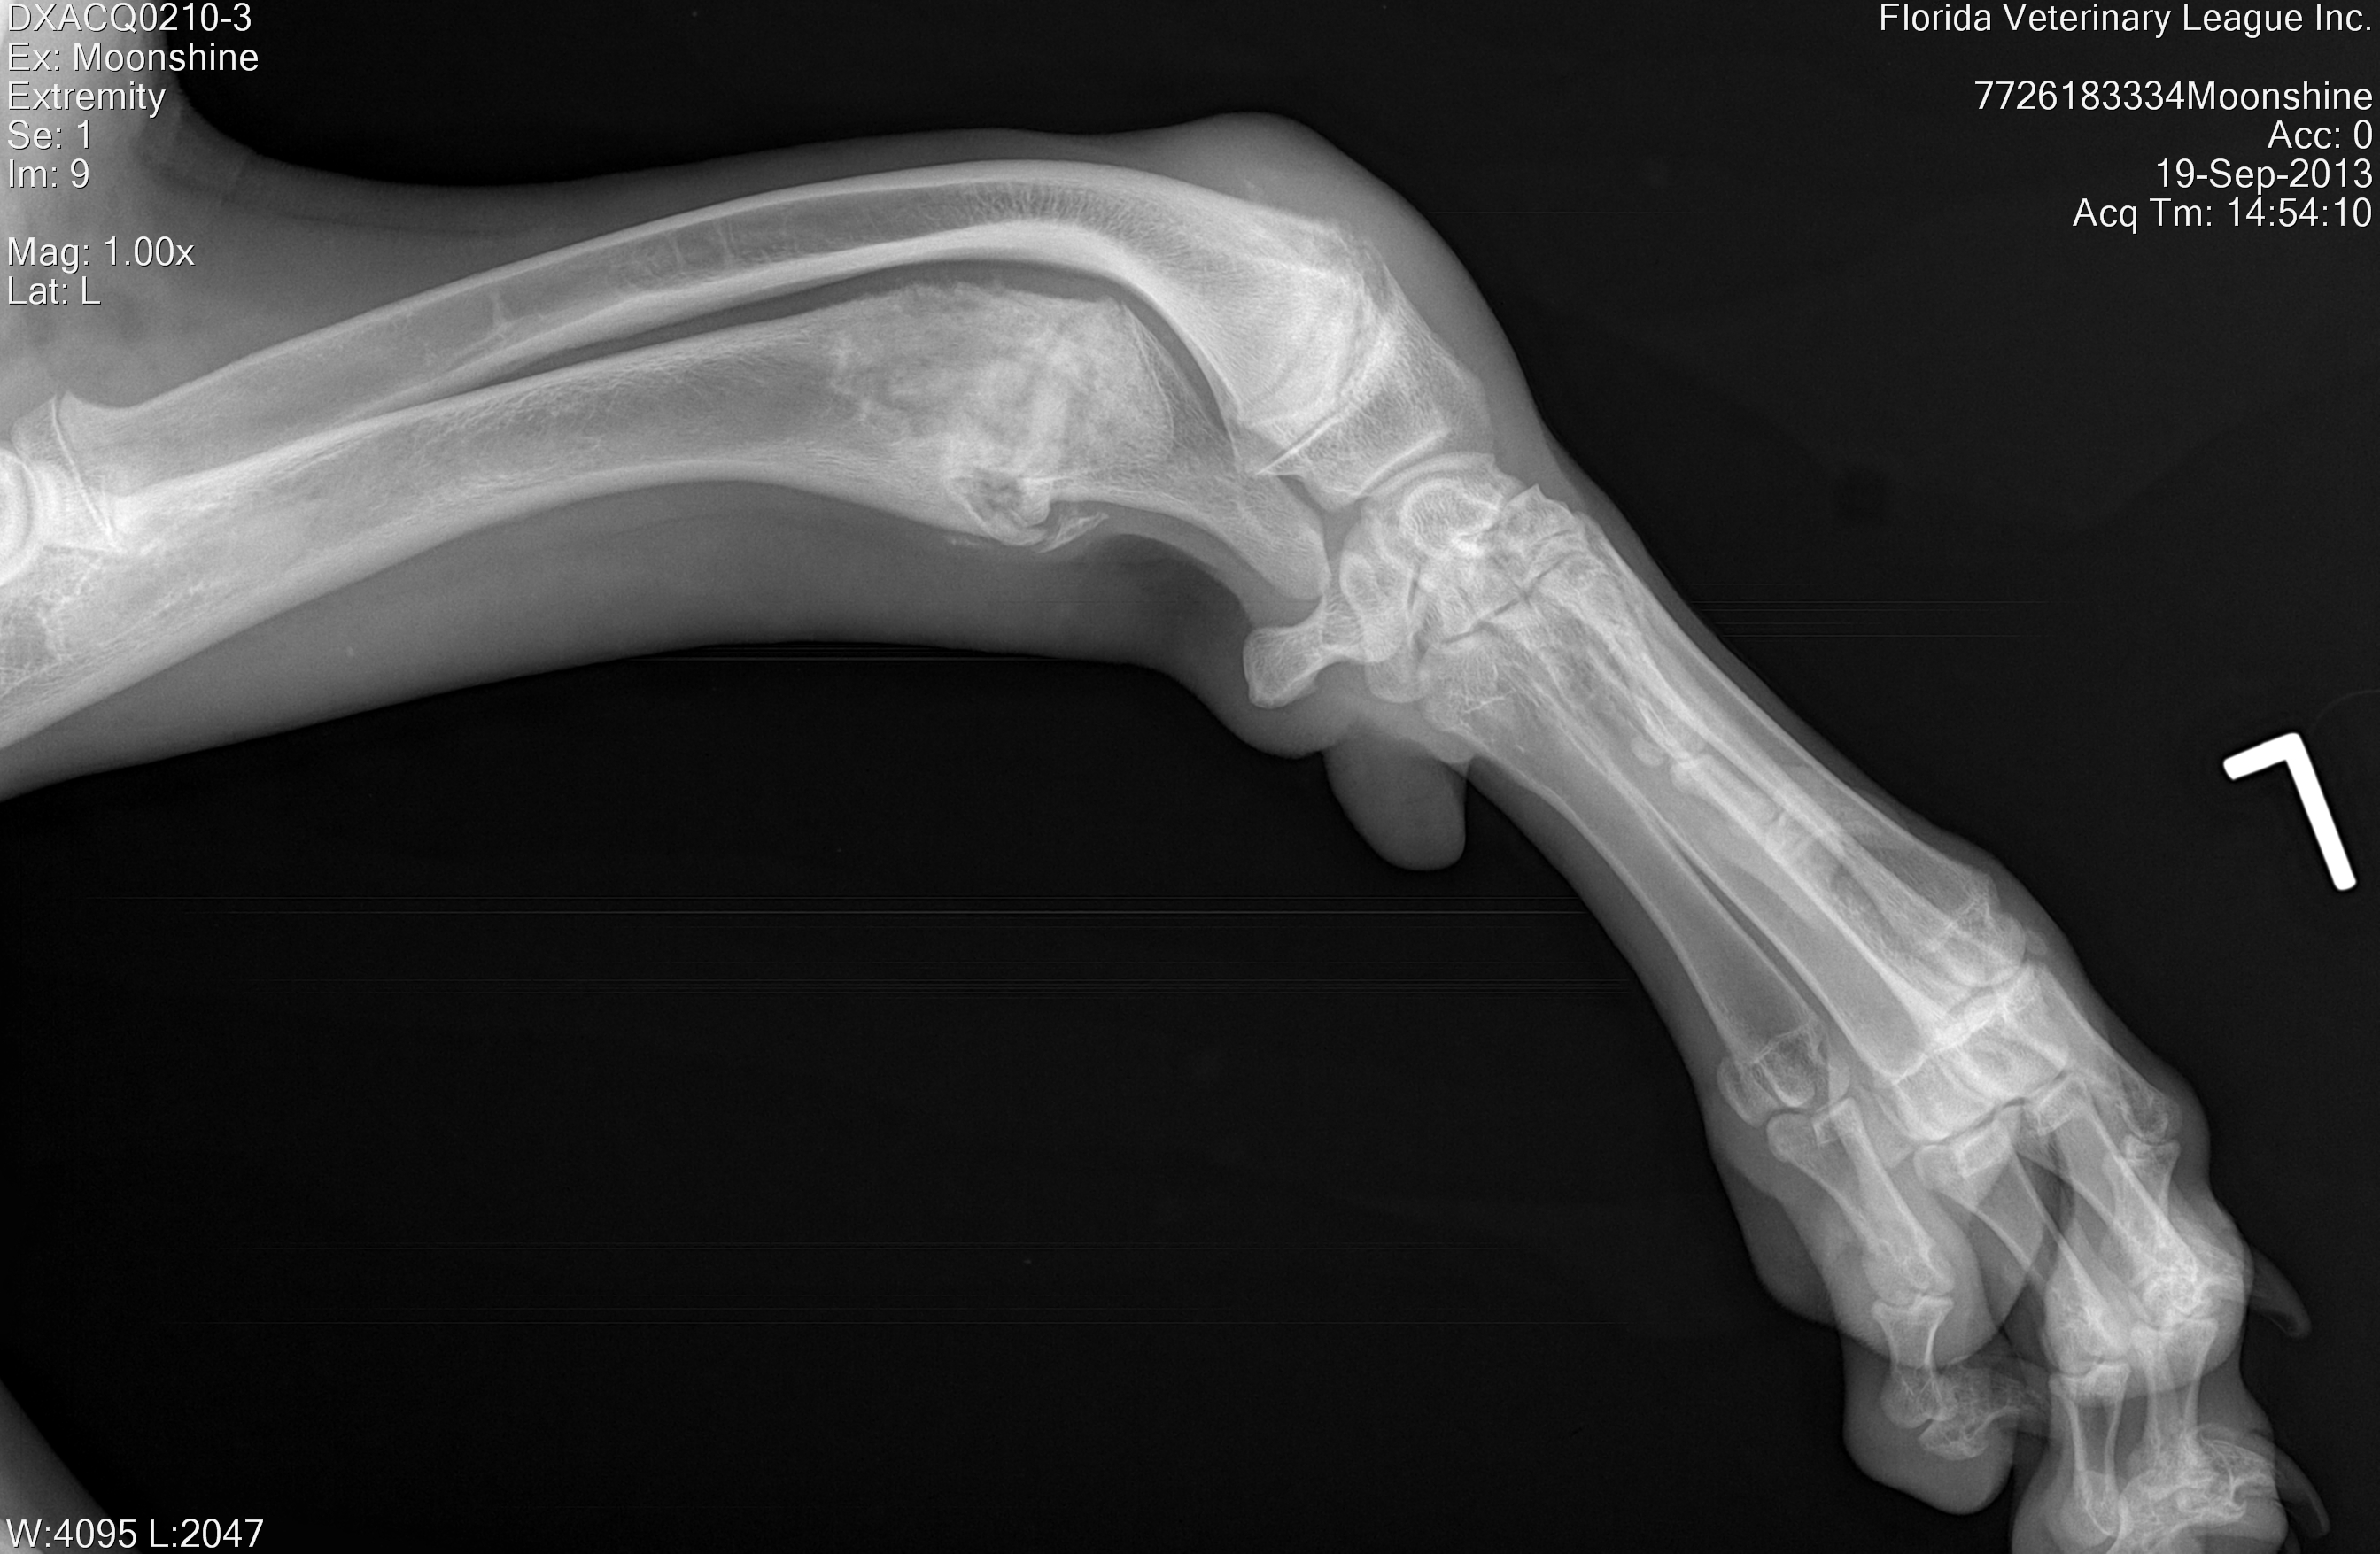

MOONSHINE:

September 19th, 2013

Moonshine is one of the most heartbreaking cases we have recently seen; this poor 10 month old Harlequin Great Dane girl was abandoned at an animal control facility due to a birth defect on her front legs, she was there for several months unable to be adopted and was already removed from the adoption floor (the first two pictures below were taken when we first saw her in her kennel), we simply couldn't leave her behind. Moonshine is currently scheduled to have corrective surgery in November 2013 for her first leg and mid December for her second leg.

(More updates and after surgery pictures will be updated soon)